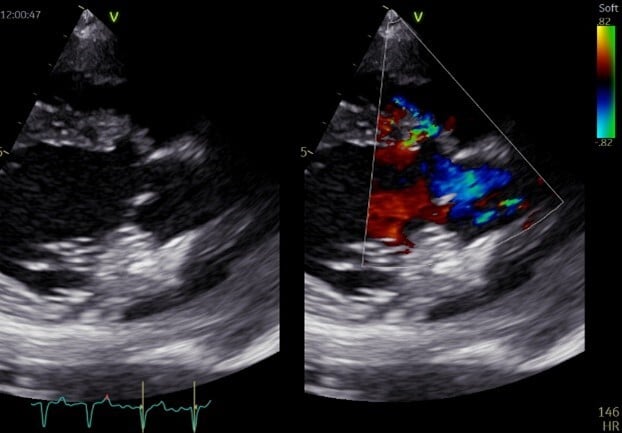

Colour Doppler is often required to detect small defects (Figure 6). This technique highlights the turbulent flow across the defect. Spectral Doppler helps our understanding of flow velocities and the presence of PHT.

Secondary changes include left atrial and ventricular enlargement, aortic insufficiency or signs of PHT in cases of right-to-left shunts (with pulmonary artery dilation and right ventricular hypertrophy).